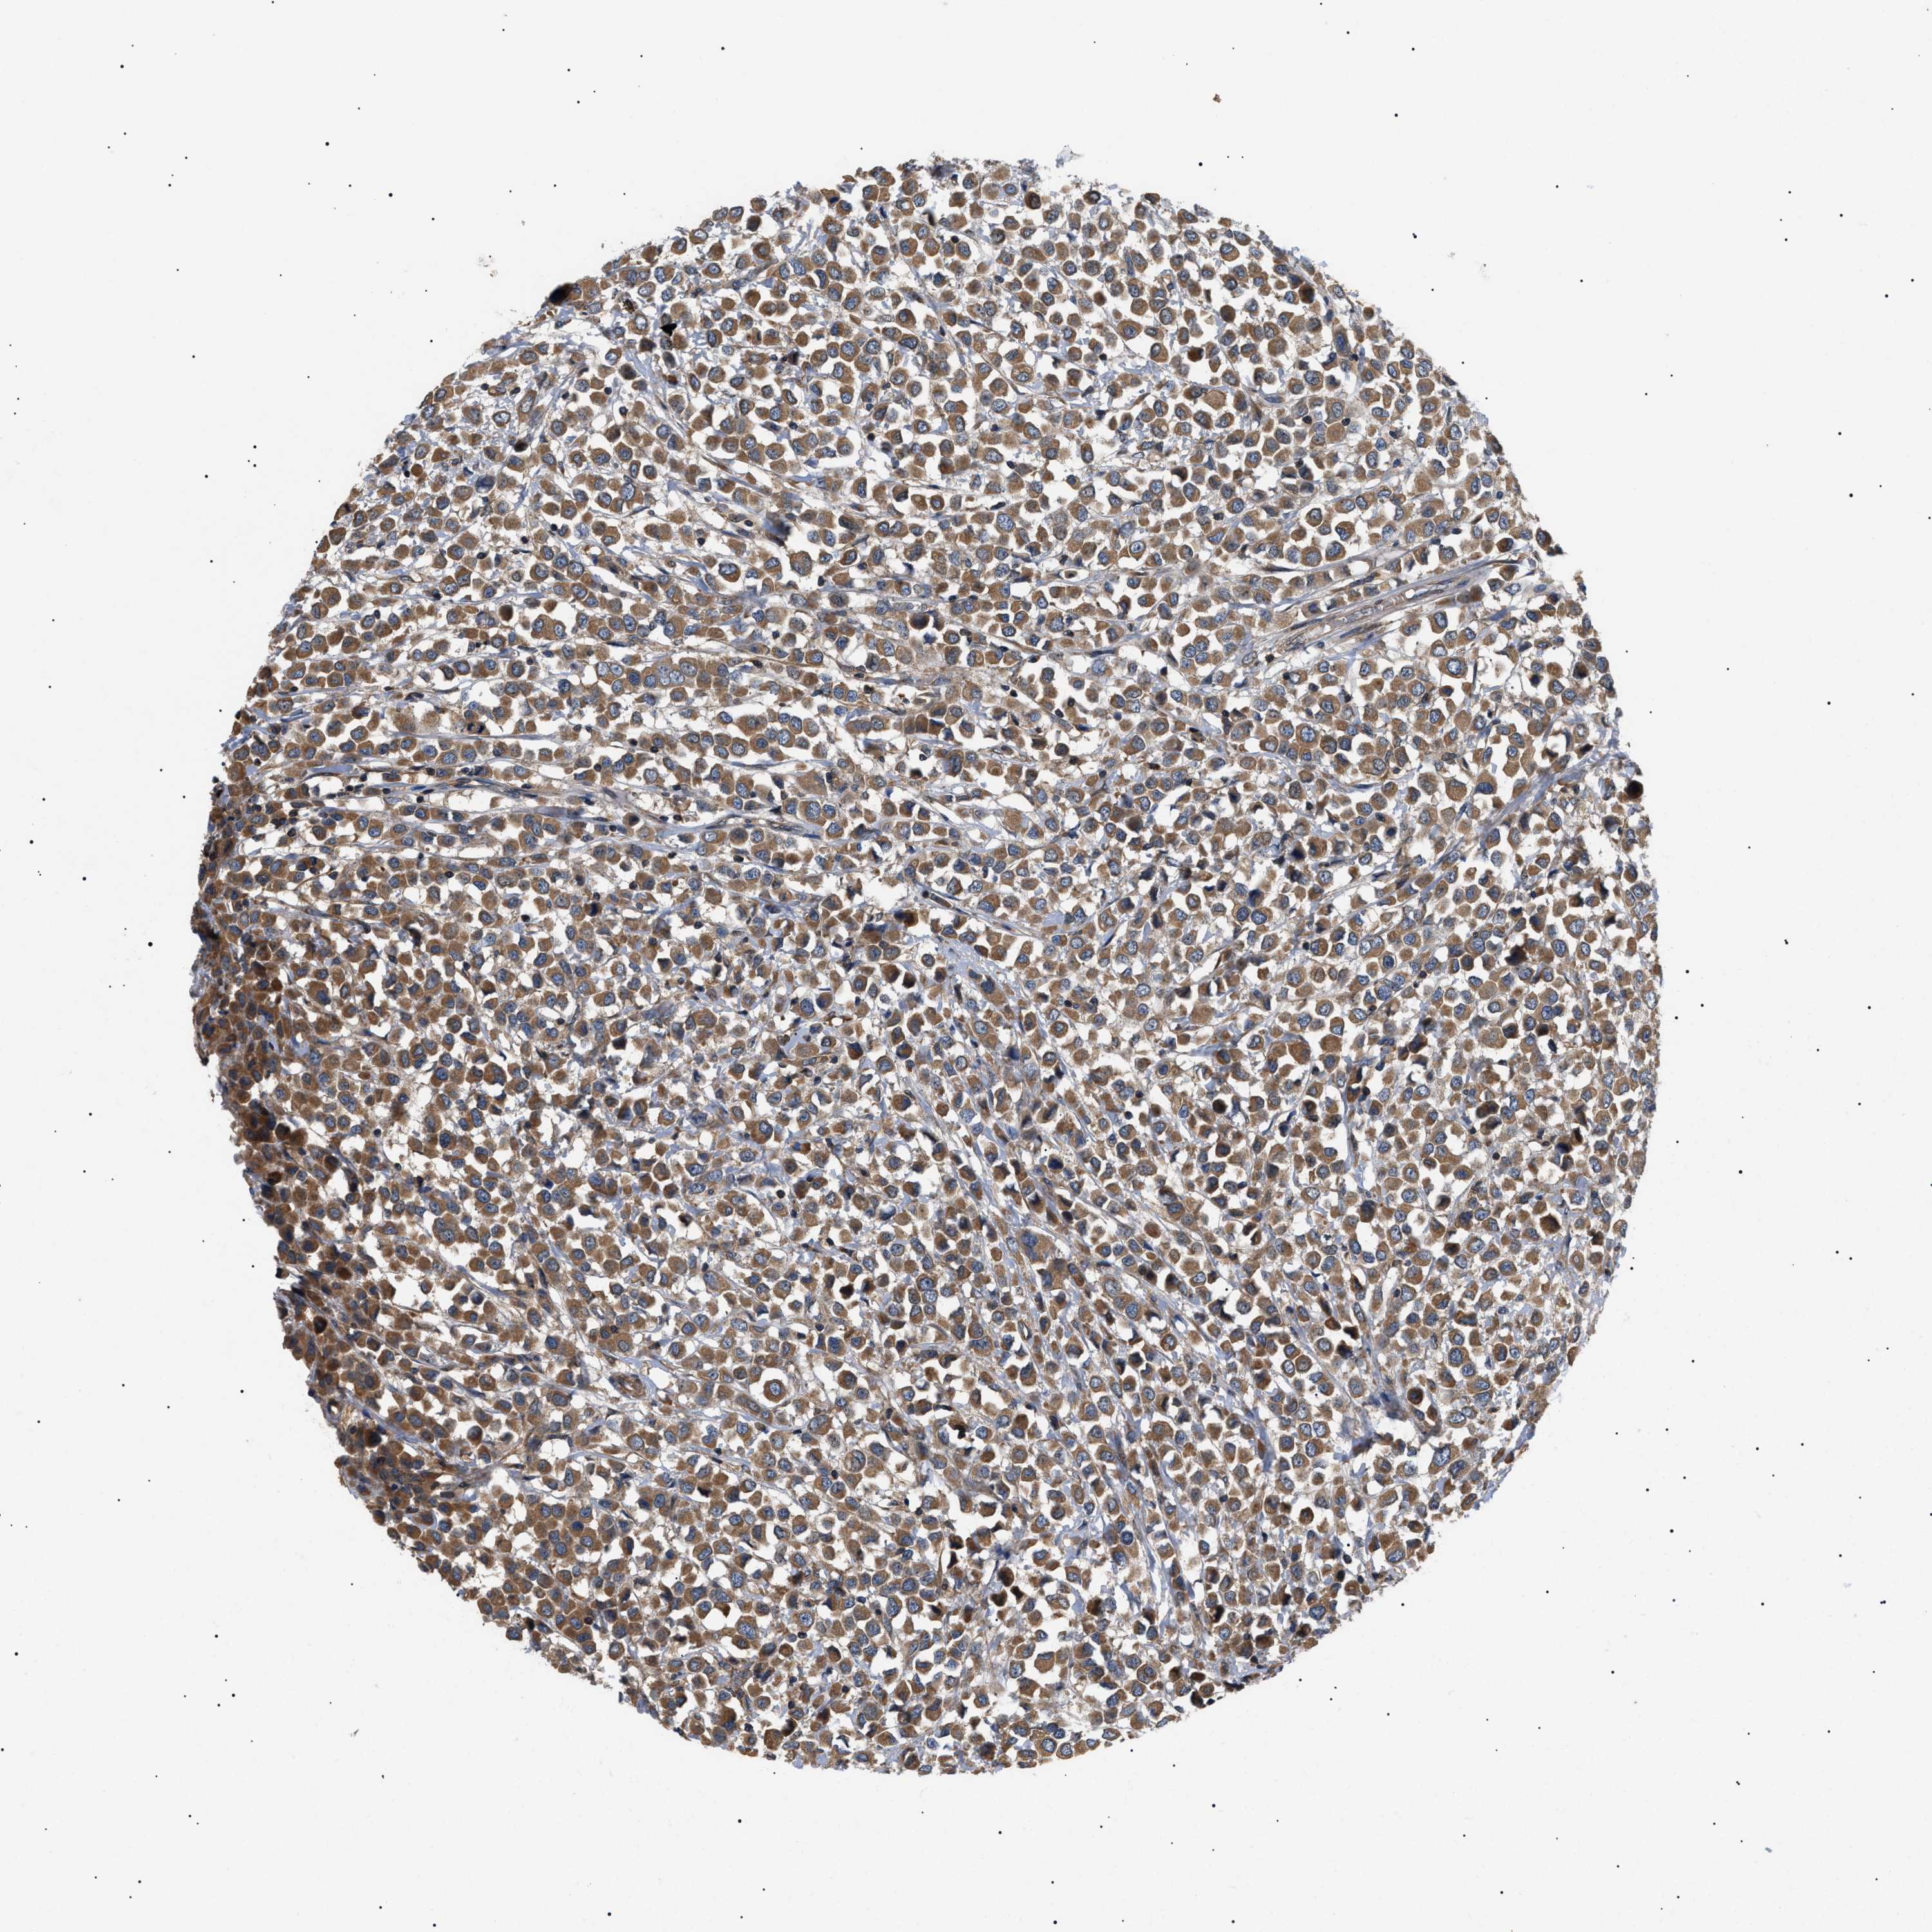

CANCER BREAST CANCER Show tissue menu

BRCA TCGA BRCA VALIDATION PROTEIN EXPRESSION